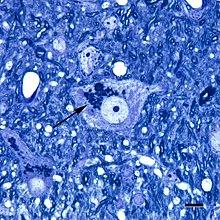

Micrograph showing a cluster of lipofuscin particles (arrow) in a nerve cell of the brain; toluidine blue stain; scale bar = 10 microns (0.01 millimeters)

Lipofuscin is the name given to fine yellow-brown pigment granules composed of lipid-containing residues of lysosomal digestion.[1][2] It is considered to be one of the aging or "wear-and-tear" pigments, found in the liver, kidney, heart muscle, retina, adrenals, nerve cells, and ganglion cells.[3]